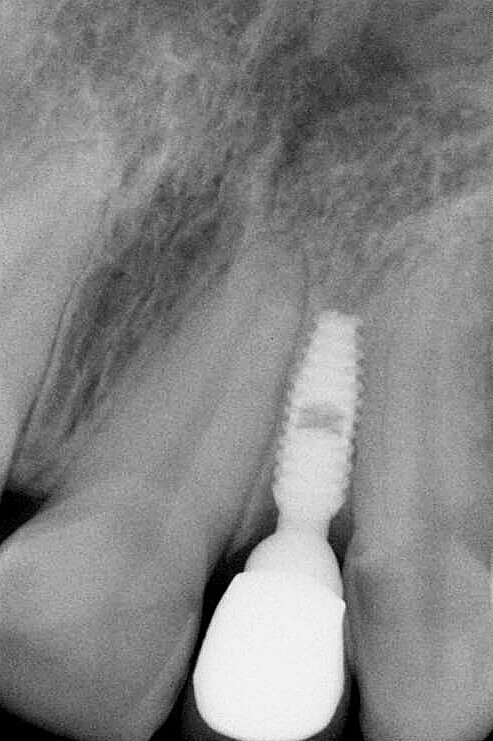

Une jeune femme de 21 ans, en bonne santé, nous a consultés pour un problème d’agénésie de l’incisive latérale gauche maxillaire. Elle avait suivi un traitement orthodontique durant trois ans au bout duquel l’orthodontiste n’avait pu obtenir qu’un espace mésio-distal de 4 mm entre le point de contact mésial de la canine supérieure gauche et le point de contact distal de l’incisive centrale gauche maxillaire. L’analyse de la radiographie périapicale numérique a montré qu’au-delà des six premiers millimètres sous le niveau de l’os crestal, 2,7 mm seulement séparaient les racines des deux dents, et après 8 mm, la distance n’était plus que de 2,1 mm (Fig. 2). Nous avons conseillé un second traitement orthodontique à la patiente, mais elle a refusé et nous avons donc discuté de la pose d’un implant étroit par la technique d’ouverture de l’espace inter-radiculaire. L’implant avait un diamètre de 3 mm, une longueur de suivantes : implant Press-Fit inséré dans l’ostéotomie ; design en plateau sans filetage ; épaulement incliné assurant un diamètre inférieur au niveau du col (selon le concept dit du « platform-switching ») ; positionnement sous-crestal à 1–3 mm sous le niveau de l’os crestal. La patiente a été anesthésiée par une injection d’articaïne et d’épinéphrine (Septocaïne, Septodont), et une légère incision crestale au moyen d’une lame de bistouri de 15c a été réalisée. Le foret-guide a été utilisé à une vitesse de rotation de 1 100 tr/min afin de perforer l’os cortical jusqu’à une profondeur approximative de 4 mm. Un alésoir manuel de Ø 2,5 mm puis un second de Ø 3 mm ont été utilisés pour effectuer pour ouvrir l’espace entre les racines.3, 4

Fig. 7 : Présentation radiologique de la technique d’ouverture de l’espace interradiculaire. Il faut noter l’insertion des alésoirs manuels de 2,5 mm et 3,0 mm entre les racines, afin de préparer l’espace pour l’implant de Ø 3,0 mm, mis en place à 3,0 mm sous le niveau de l’os crestal.

L’implant a été mis en place au moyen d’un instrument spécial pour l’insertion d’implant, qui permet au praticien de pousser l’implant fermement, en appliquant une pression précise dans l’ostéotomie (Fig. 5). La dernière étape a consisté à introduire complètement l’implant au moyen du maillet, et de l’instrument d’insertion fixé à la poignée de serrage droite. L’implant étroit était dès lors bien positionné entre les deux racines (Fig. 6). L’implant de 8 mm de long et de Ø 3 mm a été inséré par l’application d’une pression dans l’ostéotomie, et l’utilisation du maillet et de l’instrument d’insertion à 3 mm sous le niveau de l’os crestal (Fig. 7). La seconde phase du traitement a été réalisée après six mois de cicatrisation et a consisté à désenfouir l’implant. Un pilier ayant un corps de Ø 2 mm et une base hémisphérique de Ø 4 mm a été choisi pour connecter les couronnes provisoires à l’implant. Il est important de veiller à la bonne cicatrisation du tissu mou autour du contour coronaire adéquat, et celle-ci peut être obtenue par une modification du profil d’émergence de la couronne provisoire jusqu’à la formation des papilles. Après la cicatrisation complète du tissu mou, la dernière empreinte a été prise et la couronne définitive a été scellée sur le pilier en titane (Figs. 8 et 9).